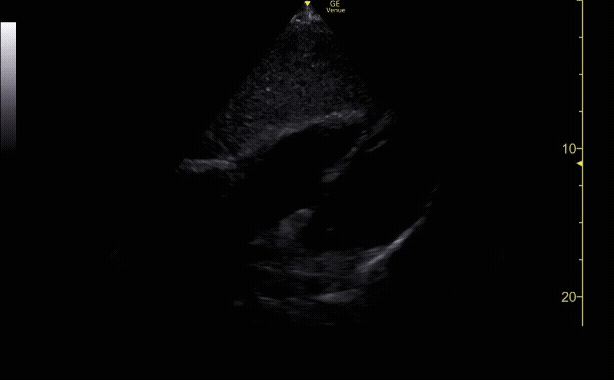

Apical 4 Chamber view with the left side of the heart on the right hand of the screen.

c/o Colleen Andrews, MD